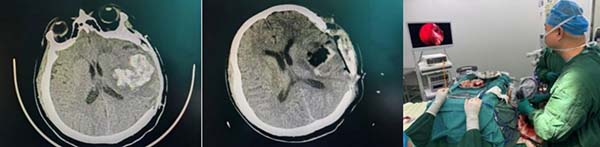

时间就是生命,延误将加重神经功能损伤。接诊团队争分夺秒完成患者转运及术前准备,全程无缝衔接抢占黄金救治时间。此次救治的关键,是启用了望京医院神经外科有史以来首例神经内镜辅助血肿清除术,这一前沿微创技术的落地,标志着科室脑出血救治迈入精准化、微创化新阶段。手术中,胡主任带领张腾飞医生、李志东医生在神经内镜精准引导下,避开重要神经血管高效清除颅内血肿。手术室麻醉医生侯进才、胡新月在饱胃情况下实施麻醉,护士关美玉、李赫默契配合器械与护理工作,为手术顺利推进注入关键保障。

得益于多学科协作与新技术应用,手术圆满成功。患者术后即刻清醒,意识快速恢复,复查CT显示颅内血肿清除效果理想,目前患者已转入康复阶段,神经功能逐步恢复。